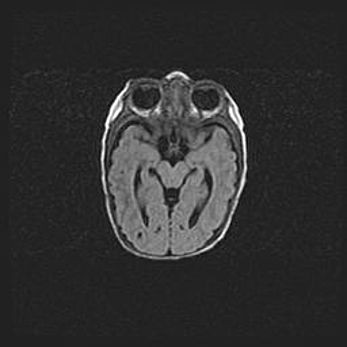

Неполная лизэнцефалия (пахигирия). Открытая гидроцефалия.

Возраст: 17 дней

Вес: 3110 г

Пол: мужской

Окружность головы: 33,5 см

Срок гестации: 35-36 недель

Лизэнцефалия—недоразвитие корковой пластинки и мозговых извилин в результате нарушения миграции нейронов коры. Поверхность мозговых полушарий гладкая. Микроскопически выявляется отсутствие нормальных слоев коры и скопление групп нейронов в подкорковом белом веществе.

Пахигирия—уменьшение числа вторичных извилин. В пораженном полушарии нервные клетки образуют толстый недифференцированный слой с неправильно расположенными нервными волокнами и группами гетеротопных клеток. Нервные клетки незрелые. Белое вещество истончено. При этом нередко аномально развит корково-спинномозговой путь.